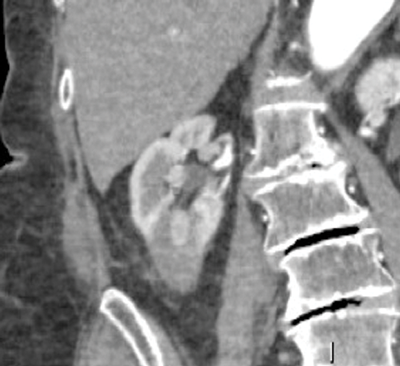

Once the probes are appropriately positioned it may be necessary to protect vulnerable adjacent structures, such as the bowel, pancreas or ureter. The adjunctive techniques most commonly employed to achieve this protection involve the injection of fluid (hydrodissection) or gas (air dissection) to displace at risk structures (Figure 3).

Figure 3: Peri-treatment image depicting cryoprobes within the iceball

and a protective layer of contrast tinted hydrodissection.

In addition the tumour can be manually levered away from the ureter once the tumour has frozen to the probes (commonly termed a ‘stickshift’ or ‘stickfreeze’). Once the probes are positioned our standard double freeze-thaw treatment cycle consists of a 10-minute freeze, 8-minute thaw, and a second 10-minute freeze. The evolving ice ball is visible on CT and imaged during the treatment cycle where it should be seen to consume the target tumour with three-dimensional treatment margins of at least 5mm. Critically, the radiologist has direct control of the power of each probe allowing manipulation of the size and morphology of the ablation zone as it forms.